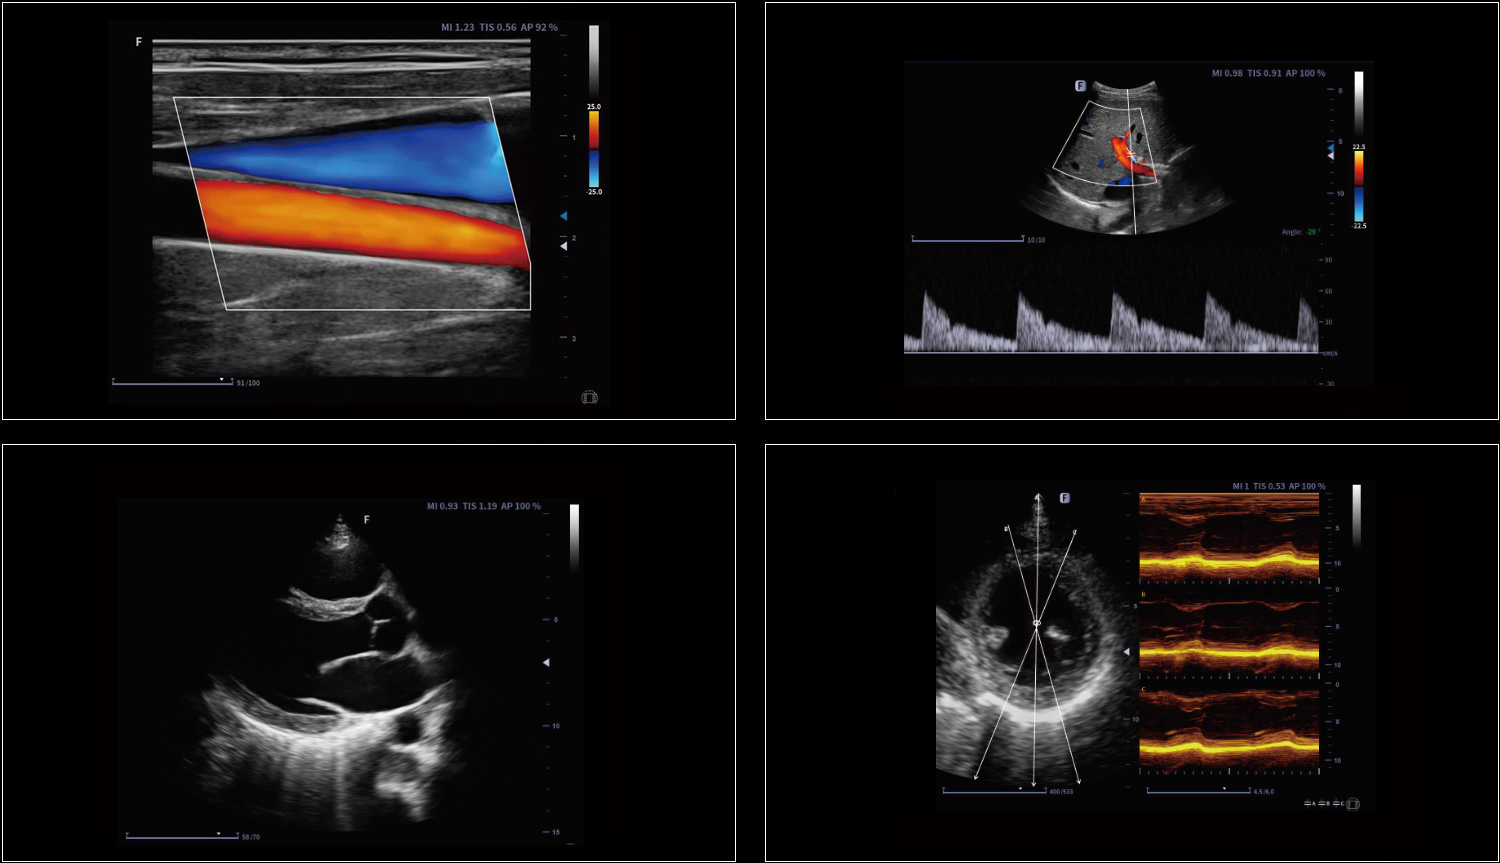

Technologia krzywoliniowego M-Mode (CAM) umożliwia wyświetlanie wszystkich przestrzennych i czasowych relacji ruchów segmentów mięśnia sercowego podczas cyklu sercowego w sektorze skanowania. Zapewnia to nową metodę pomiaru do ilościowej analizy zaburzeń ruchów segmentów mięśnia sercowego podczas fazy skurczowej lub rozkurczowej.

Obrazowanie tkankowe metodą Dopplera (TDI) to solidne i powtarzalne narzędzie echokardiograficzne, które wykorzystuje efekt Dopplera do oceny charakterystyk ściany mięśniowej w całym cyklu sercowym, obejmując prędkość, przemieszczenie, deformację oraz timing zdarzeń. Pozwala na ilościową ocenę zarówno globalnej, jak i regionalnej funkcji oraz timing zdarzeń miokardialnych.

Measure the blood vessel area, the blood flow velocity could be measured by spectrum automatically, then the blood flow volume results will show.

Automatic identification and measurement of intima-media thickness. Both left and right blood vessels, anterior and posterior walls can be measured.